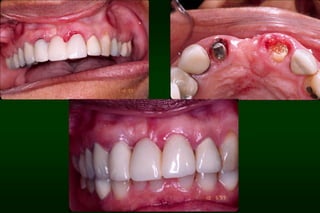

Requirements of Provisional Restoration I. Biologicrequirement: • • • • • Protect the dental pulp Maintain and contribute to the periodontal health Provide comfortable, functional occlusal relationship Maintain tooth position Protect remaining tooth structure

Types of Provisional Restoration II.Customized resin restorations 1. Direct technique • • Initial polymerization occurs intraorally Final polymerization occurs extraorally

Types of Provisional Restoration II.Customized resin restorations 3. Indirect-direct (combination) technique 1. 2. 3. 4. 5. 6. 7. Advantages: Allows trial of esthetics, function and speech Provides template for the definitive restoration Ensures color stability Allows incorporation of reinforcement Saves chair time Permits removal and immediate replacement of nonsalvageable teeth Permits long-term treatment